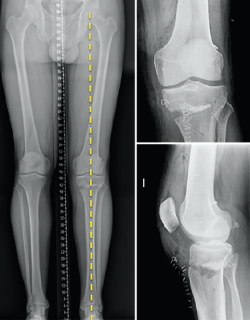

No debemos olvidar que, si bien la indicación de la osteotomía parte de la corrección del varo (plano coronal), la osteotomía afectará también a los planos sagital y axial (Figura 5).

Figura 5. Tomografía axial computarizada de control de una osteotomía valguizante de la tibia de apertura.